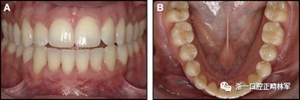

圖18.脫粘后的最終圖像:A,正面視圖; B,咬合面視圖。 進(jìn)一步的牙齒移動以糾正輕度前牙開合被認(rèn)為不符合患者的最佳利益。

圖19.A,治療前和B,治療后的三維圖像。注意牙根位置的改善和(右下圖像)右側(cè)尖牙面?zhèn)裙琴|(zhì)的形成。

這一次,病人首選一個(gè)可摘保持器。